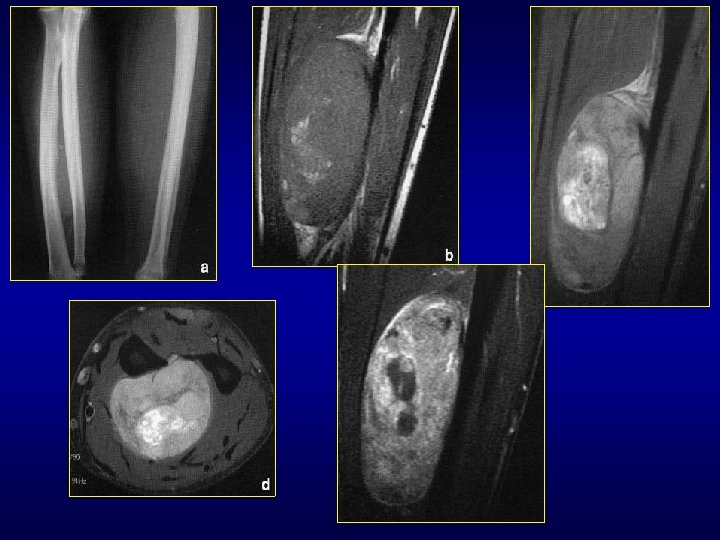

Les synovialosarcomes • Assez fréquents: 5 à 10% des T tissu mou • Adulte jeune • Région para-articulaire, proche gaine tendineuse, bourse synoviale, capsule • Membre inf: 60% (Cuisse et genou: 30%) • Masse + douleurs fréquentes • Rx et écho puis IRM +++ : limites, rapports avec tendons, capsule, gaines, bourses • Réhaussement signal en dehors zones nécrotiques et kystiques